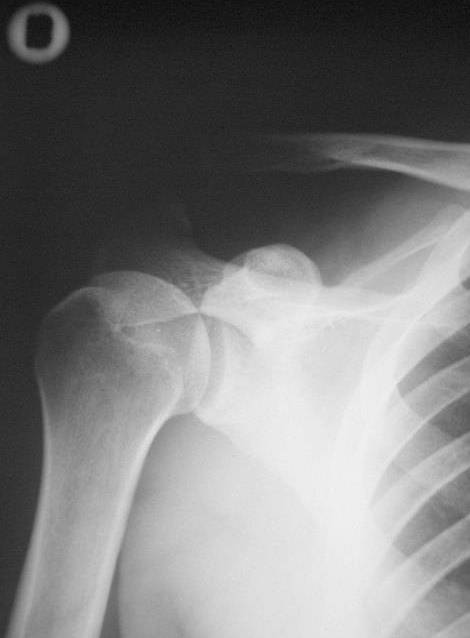

Было падение на плечо, головой вниз (в шлеме).После чего край ключицы торчит вверх, можно прижать обратно, но она возвращается в исходное положение - торчит. Болезненные ощущения только от гематомы при этом.

Ходил неделю в плотной повяке, сейчас сменили на косынку, и, в чем собственно вопрос, уверяя что через пару недель боль пройдет, а то что ключица торчит - это ни на что не влияет, просто не красиво. Можно сделать операцию в любое время, когда пройдет плечо (рукой больно шевелить).

Необходима немедленная операция и так ли все на самом деле как сказал местный доктор?

Операцию сделать можно и пораньше, и попозже. Есть неплохие шансы на приемлемый результат без операции. Если же результатом неоперативного лечения будет болезненная нестабильность, то и принять решение об операции.